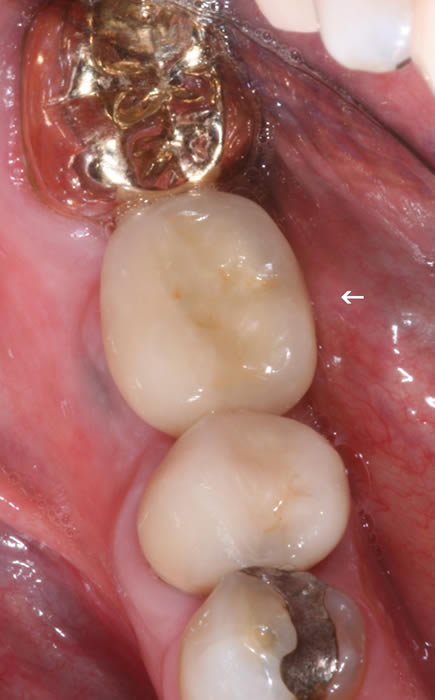

More back teeth replaced by dental implants

Case Three (2 images)

Case Four (4 images)

Case Five (4 images)

Case Six (8 images)

Case Seven (4 images)